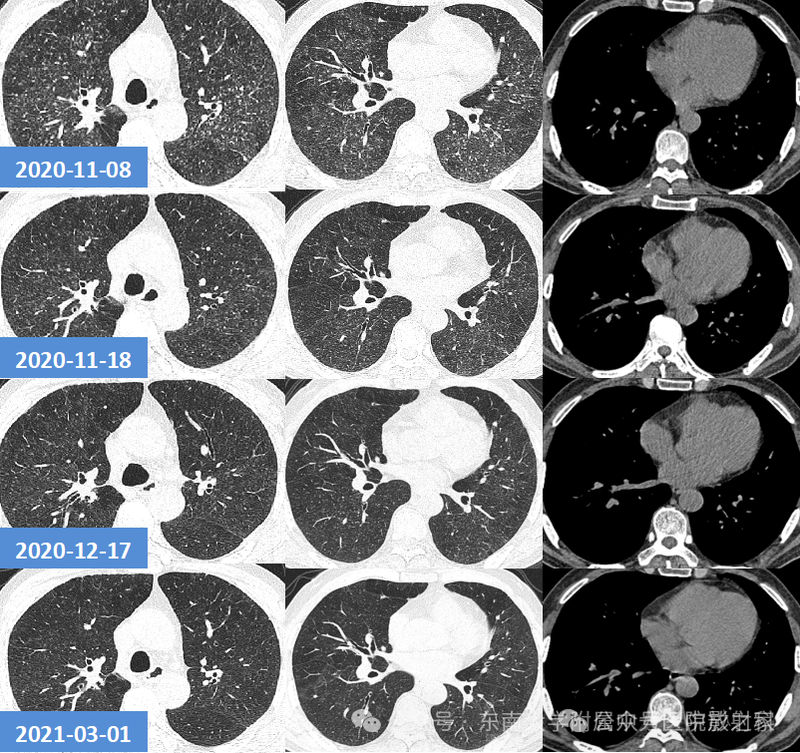

一、结节肿块型

1、部位:一般位于胸膜下,背侧胸膜下为主,两下肺明显,上肺偏少(3/4位于下叶 )

3、大小:结节较小,多为2cm以下;

4、边缘:绝大部分边界清楚,边缘可见平直征、刀切征,可以有细小毛刺,比较纤细,多为晕征中毛刺,相对收缩力偏弱;少数病人收缩比较明显

5、密度及强化:实性部分密度均匀,约1/3内部可见空泡征、实变中的空洞或空腔(可以单个内壁光滑,也可以多分隔)、含气支气管征;增强后均匀强化(强化轻到中度)延迟强化;

6、与血管的关系:2/3近端与血管相连,部分血管自然穿过;

7、晕征:1/3有晕征,晕多范围较小,个别晕较大。